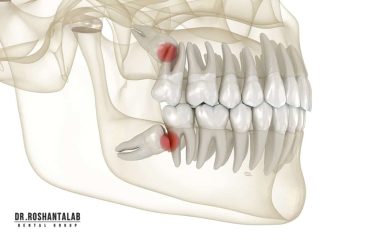

🔸جراحی پیشرفته نظیر سینوس لیفت